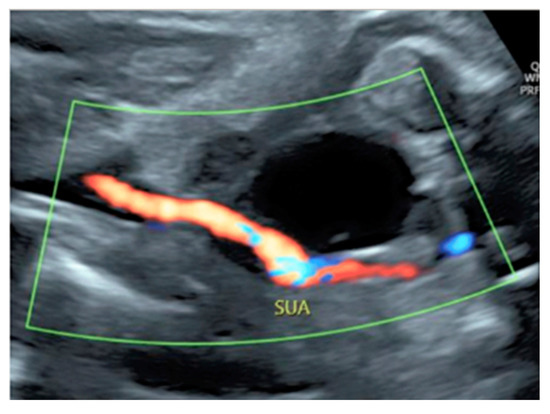

3.2.10. Single Umbilical Artery